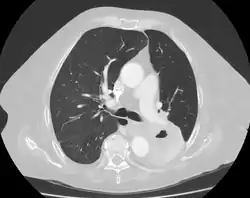

Diagnosis of a lung cavity is made with a chest X-ray or CT scan of the chest,[2] which helps to exclude mimics like lung cysts, emphysema, bullae, and cystic bronchiectasis.[5] Once an imaging diagnosis has been made, a person’s symptoms can be used to further narrow the differential diagnosis. For example, recent onset of fever and productive cough suggest an infection, while a chronic cough, fatigue, and unintentional weight loss suggest cancer or tuberculosis.[2] Symptoms of a lung cavity due to infection can include fever, chills, and cough.[5] Knowing how long someone has had symptoms for or how long a cavity has been present on imaging can also help to narrow down the diagnosis. If symptoms or imaging findings have been present for less than three months, the cause is most likely an acute infection; if they have been present for more than three months, the cause is most likely a chronic infection, cancer, or an autoimmune disease.[5]